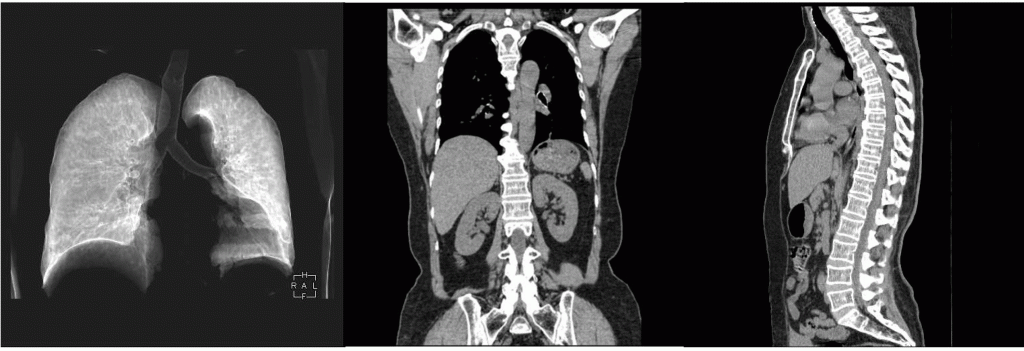

CT装置

16列マルチスライスCT装置です。マルチスライスCT装置とは、一回転の撮影で複数断面の撮影が同時に行えるCT装置のことです。従来の装置と比較すると、広範囲の撮影を短時間で行うことができるため、検査中の息を止める時間も短くなり、患者さまの負担が小さくなりました。さらには最薄で0.625ミリメートル厚という詳細な画像データを得られるようになり、小さな病変でも描写できるようになりました。